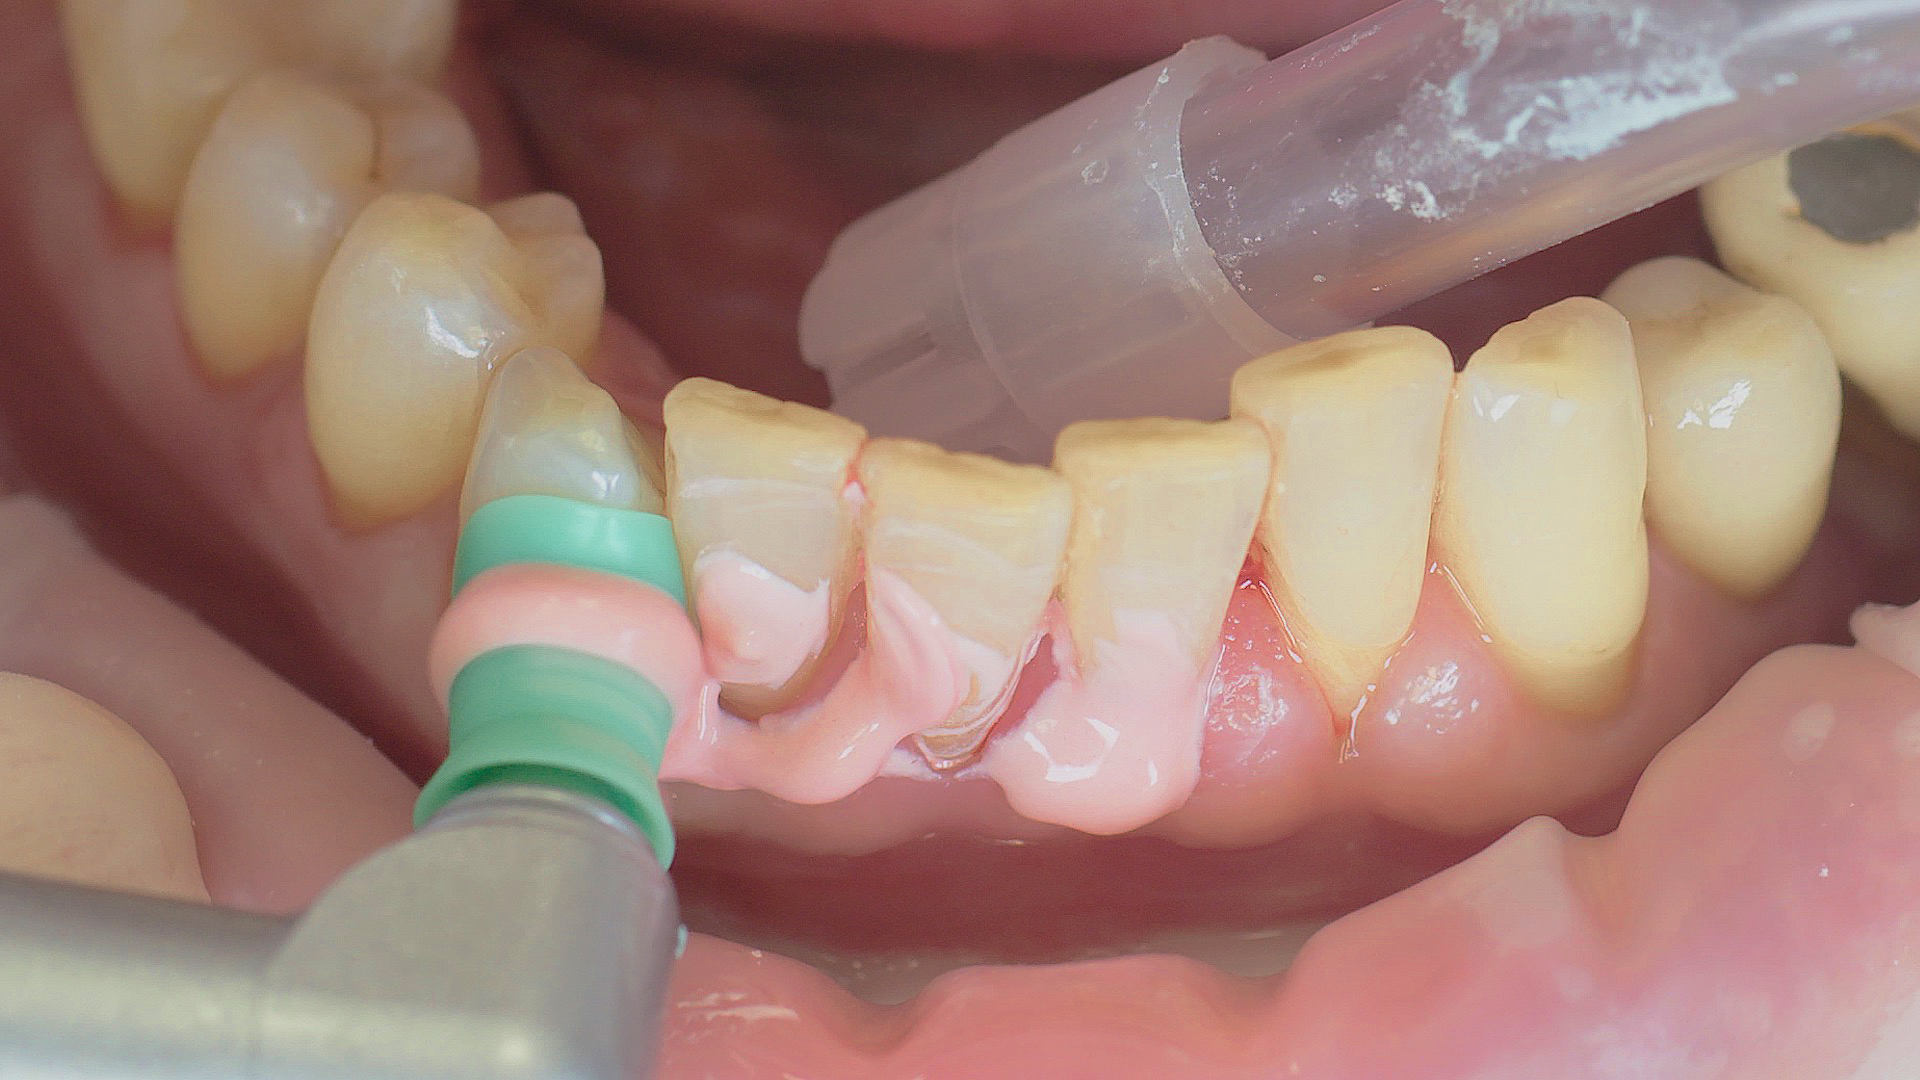

Where necessary, initial periodontal treatment is carried out. First, professional tooth cleaning establishes healthy gingival conditions. In this procedure, calculus (Fig. 1) and biofilm (Fig. 2) are removed as far as the gingival sulcus. In combination with careful instruction on oral hygiene, this gives the patient the basis for long-term freedom from inflammation.15